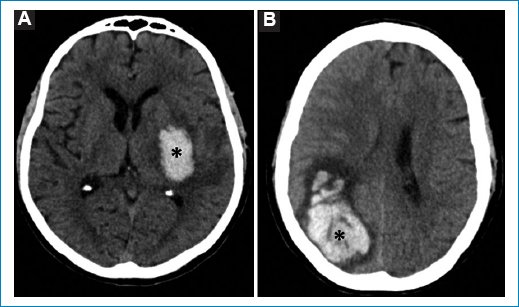

Respecto a los cinco pacientes con hallazgos patológicos agudos en la TCC, cuyas características demográficas y clínicas se describen en la tabla 2, se reconocieron un ACV isquémico agudo en el territorio de la arteria cerebral media derecha (Fig. 1), un edema cerebral difuso por encefalitis (Fig. 2), una encefalopatía necrotizante aguda (Fig. 3) y dos hematomas intracraneales intraaxiales, de los cuales uno en se ubicó en los núcleos de la base del hemisferio cerebral izquierdo y el otro en el lóbulo parietal derecho (Fig. 4). Todos ellos correspondieron a cuadros de dengue grave.

Figura 3. TCC de un paciente de 37 años con encefalopatía necrotizante aguda, en la que se observa hipodensidad de ambos tálamos, tronco cerebral y cerebelo por edema (asteriscos). Nótese además el colapso del cuarto ventrículo (flecha). Imágenes axial (A) y sagital (B).